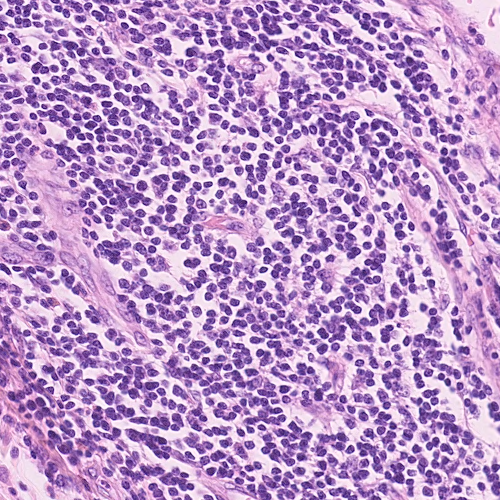

We train and test SP-CNN and TSP-CNN on two colon cancer datasets: 1) publicly available UW Dataset [5] which includes H&E stained histology images of colorectal adenocarcinomas. There are a total number of nuclei marked at the nucleus center (please refer to Sec. VII.A. of [5] for more information). Our choice of the UW Dataset is because it represents real-world challenges such as overlapping nuclei and contains other shapes that are often confused with nuclei. Further, it is one of the few publicly available datasets that is widely used in many recent deep learning-based nuclei detection methods [5, 19, 46], 2) a new dataset carefully prepared and labeled manually by medical experts at the Center for Molecular Immunology and Infectious Disease, Penn State University. We call it the ‘PSU Dataset’ and it includes images of colon tissue from pigs at a resolution of m/pixel. Formalin fixed paraffin embedded pig colon sections were deparaffinized and stained with fluorescent DNA stain DAPI (4’,6-diamidino-2-phenylindole) to visualize the cells as described in [47]. The selected images represent cross-sectional view of the colon epithelial cells. It also comprised of areas with artifacts, over-staining, and failed auto focusing, to represent outliers normally found in real scenarios. A total number of nuclei are annotated manually by an expert. For reproducing research results, we have made this dataset publicly available at the SP-CNN web-page [29]. Sample images from both datasets are shown in Fig. 8.